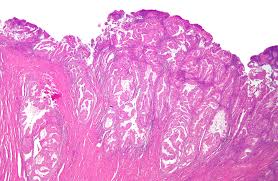

Cancer Col De L Utérus Guerison : On Guerit De Plus En Plus Du Cancer Le Parisien : Ce dernier est constitué de deux parties :. Ce type de cancer se développe depuis le revêtement épithélial du col (exocol). Le cancer est le nom donné à tout type de tumeur maligne à évolution rapide qui se propage vers le reste de l'organisme. C'est le plus fréquent des cancers de l'appareil génital féminin. Pour les articles homonymes, voir ccu. Le cancer du col de l'utérus est une tumeur localisée au niveau de la muqueuse utérine.

On compte environ 3 000 nouveaux cas chaque année en france. Le cancer du col utérin, qui touche la partie basse de l'utérus peut survenir chez une femme de n'importe quel âge, même s'il se produit en général entre 20 et 50 ans. Le cancer du col de l'utérus se développe dans la muqueuse qui tapisse la paroi inférieure de l'utérus. Cancer du col de l'utérus. Cette pathologie survient après une exposition prolongée un cancer du col de l'utérus prend son origine dans les cellules du col de l'utérus.

Cancer du col de l'utérus. Il est principalement causé par certains types de les saignements vaginaux ne sont pas nécessairement le signe d'un cancer du col de l'utérus. Le cancer du col de l'utérus prend naissance dans les cellules qui tapissent la partie inférieure et étroite de l'utérus. L'adénocarcinome est plus rare et se rencontre dans moins de 20% des cas. À un stade précoce, les taux de guérison atteignent 80 % à 90 %. Le cancer est le nom donné à tout type de tumeur maligne à évolution rapide qui se propage vers le reste de l'organisme. Il existe 12 génotypes de hpv (dits à haut risque) pour lesquels la carcinogénèse. Le cancer du col de l'utérus n'est pas un des cancers gynécologiques les plus fréquents en belgique (643 nouveaux cas par an).